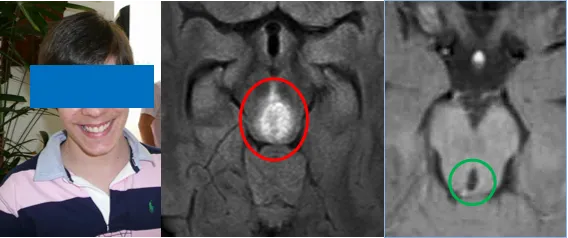

13岁的马修是大班长,他平时学习认真,稳重负责,性格开朗,和同学关系和睦。但就在学期中途,他却突然决定请一个长假。跟他关系好的朋友纷纷关心马修的情况,但马修却一反常态地沉默了。

于是,马修将不适告诉了父母,并在父母的陪同下来到医院进行检查。可是检查结果却令他们心凉了半截:脑干上存在一个明显的占位,可能为胶质瘤。

术前影像

几天后,手术如期进行,并在巴教授团队数小时奋战下取得成功,肿瘤被顺利切除。病理显示为WHOⅢ级间变性星形细胞瘤(Anaplastic Astrocytoma)。

如今,在巴教授15年的随访下,马修已经顺利成年,尽管他的童年遭遇过不幸,但一场成功的手术,为他争取到了完整的少年与青年。看着如今笑容满面、意气风发的马修,父母无比庆幸当年的选择没有给孩子造成严重的后果,反而挽救了他。